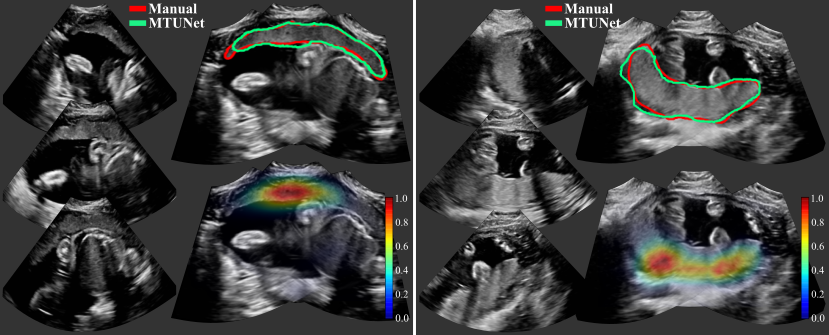

Examplary multi-view images are shown in Fig. 5 with corresponding placenta segmentations with MTUNet and combined attention maps. The placenta is better visualized in the multi-view images with reduced image artifacts and an extended FoV. The multi-task model MTUNet provides an accurate segmentation and the combined attention maps localize well the placenta. Further examples of multi-view images with corresponding segmentations can be found in Fig. 12 in the appendix.